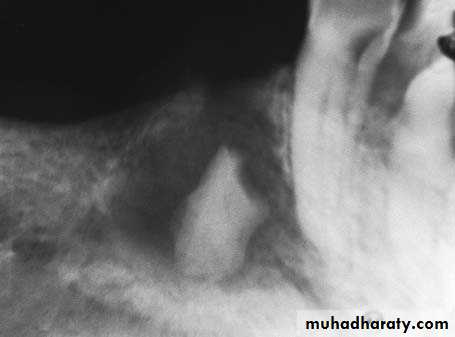

After making an L-shaped incision, the flap is reflected and a small window is created, using a round bur, with constant irrigation using saline solution, on the buccal bone, corresponding to the tip of the fractured root .

The window is then enlarged, and enough of the root is exposed to allow its displacement from the socket using a narrow-angled elevator . After removal of the root, the socket is cared for and interrupted sutures are placed

The root may also be removed though the window itself that was created on the buccal bone. A semilunar flap is created and complete or partial exposure of the root follows. The root is then removed from the bone deficit without difficulty, preferably using a narrow- angled elevator . This technique is usually used in cases of fractured small roots, which were not removed during the extraction procedure but remained in the socket for a long time and were eventually totally covered by bone.